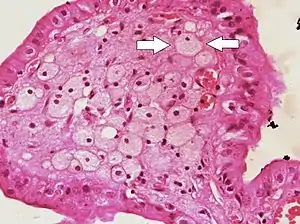

Foam cells (one indicated by arrows) visible in the finger-like projections into the gallbladder lumen in a case of cholesterolosis